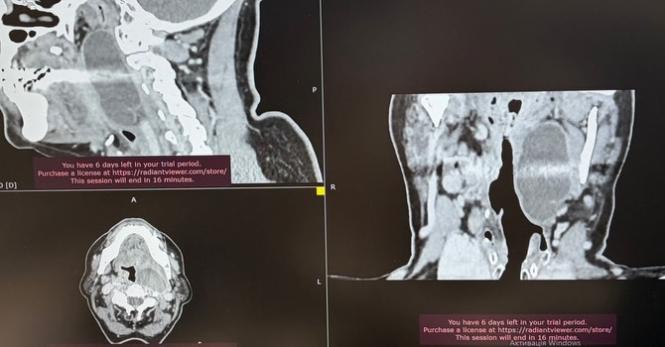

Фахівці Подільського регіонального центру онкології 16 березня поділилися історією успішного порятунку жінки зі складною патологією. Хірурги закладу провели філігранну операцію та повністю видалили рідкісне новоутворення парафарингеального простору, яке буквально перекривало пацієнтці дихальні шляхи.

Такі пухлини підступні через те, що тривалий час вони ніяк не видають своєї присутності. Проте коли новоутворення збільшується, воно починає тиснути на життєво важливі магістральні судини та нерви, що розташовані глибоко за глоткою. У цьому випадку хвороба зайшла надто далеко: жінка почала задихатися та вже не могла нормально приймати їжу. Лікарі провели ретельне планування, адже працювати довелося у надзвичайно складній анатомічній зоні. Завдяки високій кваліфікації та злагодженості всієї медичної команди, хірурги змогли повністю прибрати пухлину, не зачепивши жодної важливої структури. Зараз жінка вже оговталася від втручання та поїхала додому у задовільному стані. Вона почувається добре і надалі перебуватиме під наглядом фахівців, а цей складний випадок став ще однією перемогою вінницької медицини над рідкісними недугами.